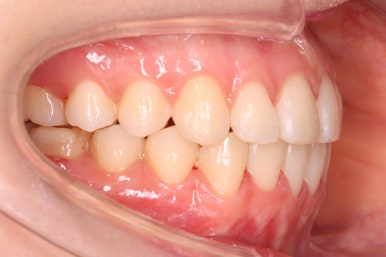

위아랫니가 매우 가지런해졌고 고민하셨던 덧니도 말끔히 개선되었습니다.

또한 비발치, 즉 발치를 안하고 덧니를 가지런하게 했음에도 입이 더 돌출되거나 뻐드러지지 않고 치료를 할 수 있었습니다.

14개월만에 치아는 가지런해졌고, 위아래 치열의 중앙도 맞아졌으며 발치를 하지 않았음에도 치열이 뻐드러지거나 돌출되지 않았습니다.

또한 오히려 부각되었던 대문니의 뻐드러짐이 치료 후 개선이 되었고 웃는 모습도 굉장히 예뻐졌습니다.